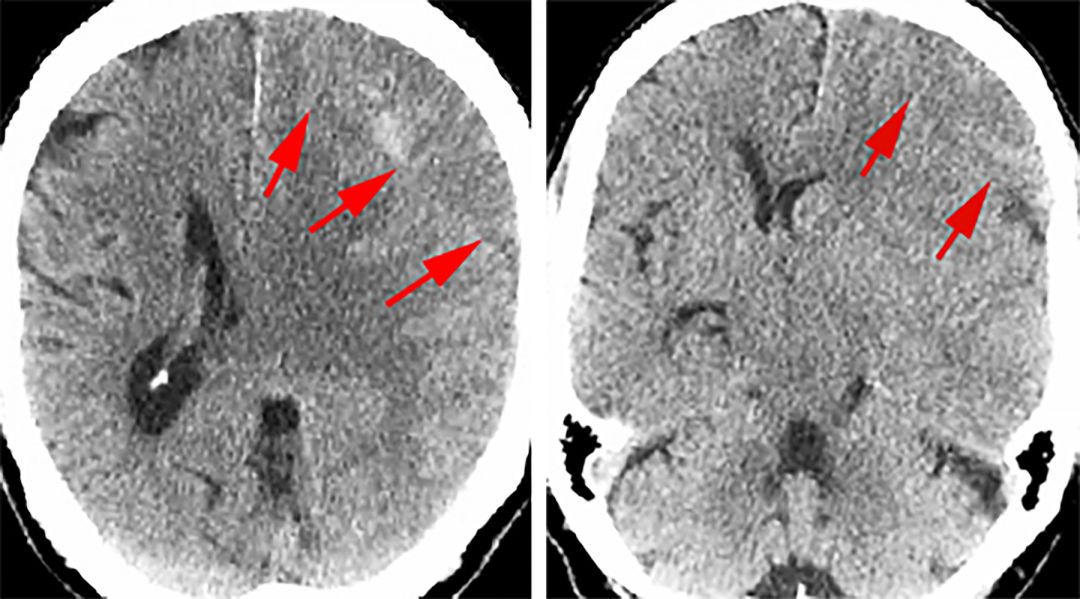

非增强CT不仅用于识别cSDH的存在,也用于明确血肿形成时间,这对选择术式有意义重大。与正常脑组织相比,aSDH表现为高密度,sSDH表现为等密度,而cSDH则表现为低密度。这种密度上的差别是由于血肿成分随时间演变而造成的。血肿通常包含一种主要成分,但同时伴有多种其他成分。

随着时间的推移,血肿的液体含量逐渐增多,导致其在CT上表现为低密度。这种血液粘度的变化也使得外科干预措施有所变化。确诊一般无需加做增强CT,但是,对于等密度的亚急性硬膜下血肿,增强CT可准确显示血肿边界。

图1. 图示左侧额叶sSDH的CT影像,病变呈等密度。红色箭头标注了血肿的边界。由于其与大脑正常组织密度相仿,因此较难判断。另外,此CT展示了SDH的占位效应导致的中线偏移。